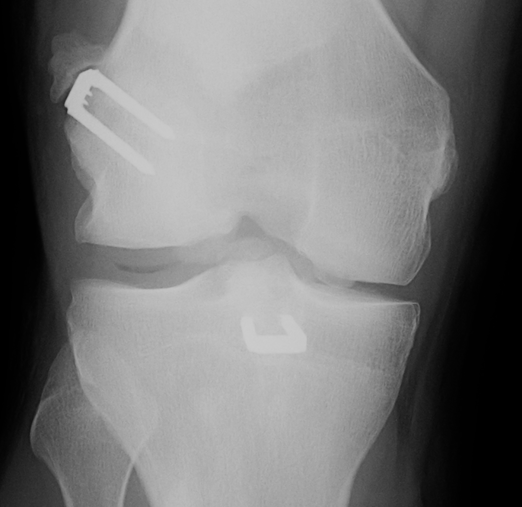

2. Extra-Articular Augmentation

Lateral extra-articular procedures

- prevent anterior subluxation LFC in extension

- unpopular due to poor long term results

1. Ellison Procedure

A. Strip of ITB Deep to LCL

- placing it anterior in a bone trough

B. Plication the capsular ligament

2. MacIntosh Procedure

ITB left attached distally

- deep to LCL

- subperiosteal tunnel in LFC

- thru intermuscular septum

- back on itself distally